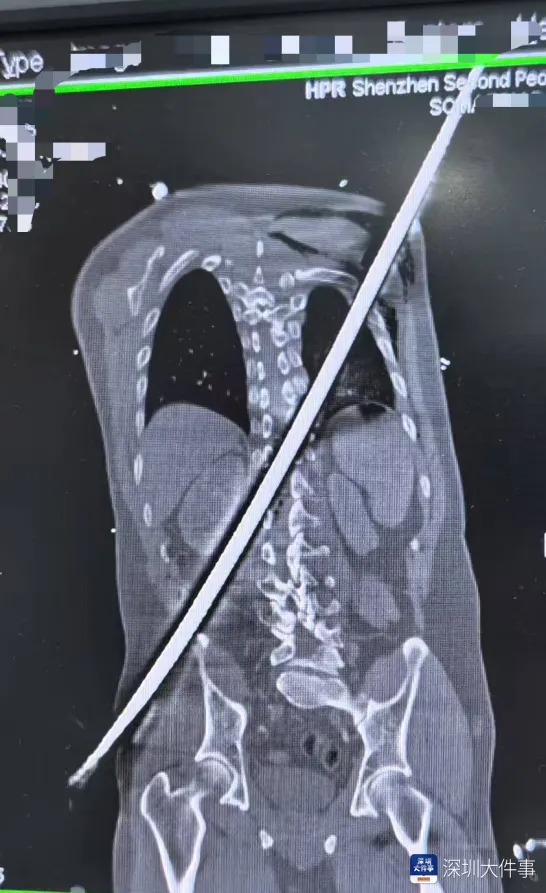

日前,一名男子被一根67厘米长的钢筋从右侧臀部刺入,斜穿身体后从左后侧肩背贯穿而出。

医院急诊科第一时间启动抗休克治疗,快速稳定患者血压,同步完善各项检查,为后续治疗筑牢基础、抢占先机。全身CT扫描精准勾勒出钢筋在体内的“行走路径”——

钢筋险之又险地穿过腹膜后间隙,击穿胸腰段脊柱椎管,最终穿入胸腔,其路径紧贴肾脏、大血管等关键脏器——每一次心跳,都可能让钢筋锋刃与血管发生摩擦,引发灾难性大出血。